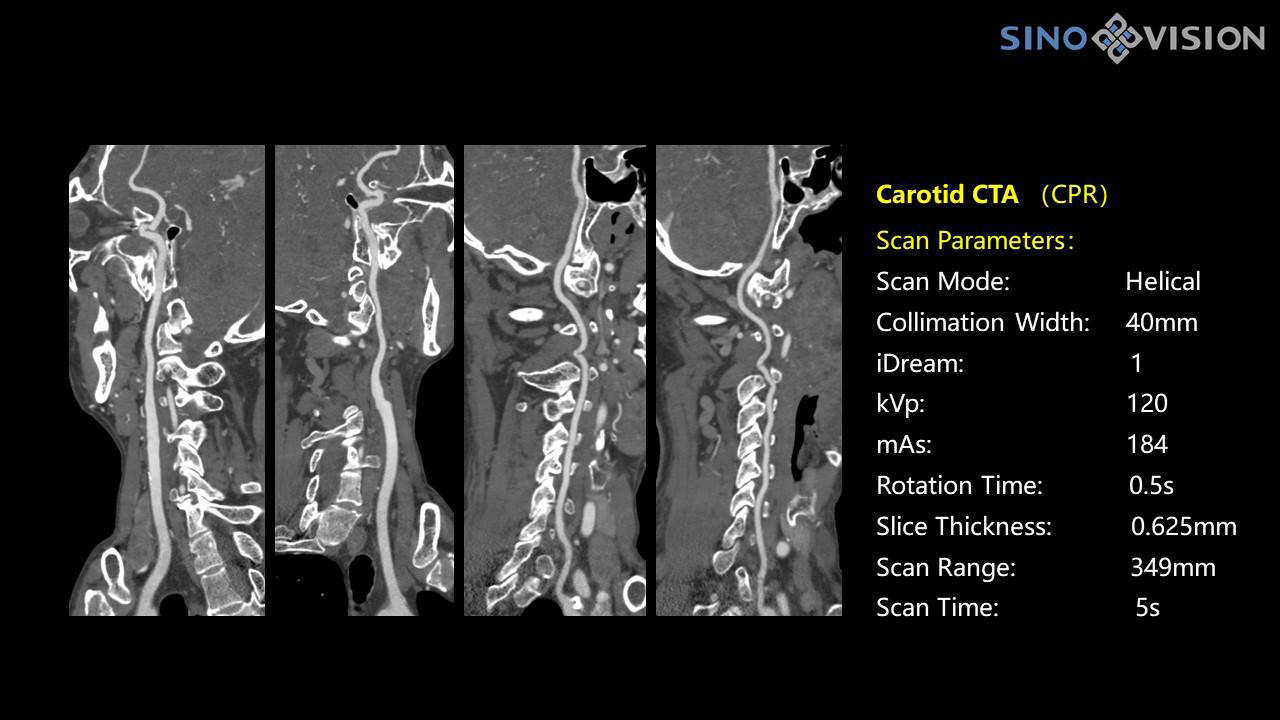

- Общий анализа сосудов на основе серии данных КТ

InsitumCT 768 является вершиной нового поколения широкоапертурных широкополосных компьютерных томографов. Этот КТ-сканер обеспечивает 128 срезов КТ при апертуре 76 см, увеличивая производительность визуализации до 21 л/см, способствуя точной диагностике и лечению заболеваний и значительно улучшая клинические характеристики и масштабируемость. Обеспечивает получение изображений высокого разрешения при низкой дозе облучения.

Компьютерный томограф Insitum CT 768 – старшая модель в линейке SinoVision Insitum. Еще более быстрый и еще более мощный, он значительно повышает пропускную способность кабинета КТ, обеспечивая при этом высококачественные исследования даже в самых сложных случаях практически во всех областях, включая кардиологию, исследования сосудистой системы, онкологию. Имеет специализированный педиатрический протокол исследования, минимализирующий лучевую нагрузку на ребенка.